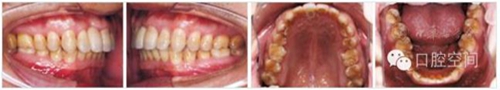

30歲男性患者,由于下前牙經(jīng)常咬傷上牙腭側(cè)牙齦,要求矯正調(diào)整咬合關(guān)系。上頜粘接直絲弓矯治器2個月后,下頜開始固定矯治,排齊牙列。4個月后下頜更換至0.018英寸鎳鈦絲,在下頜中切牙之間前庭溝處,局麻下切開黏膜,正中聯(lián)合部位植入一顆微螺釘(1.6 mm×9 mm,慈北醫(yī)療器械有限公司)。以直徑0.30 mm結(jié)扎絲連接微螺釘頭部,并穿出黏膜形成牽引鉤形狀。一周后開始加力,以微螺釘種植體支抗行閉合式牽引壓低下頜切牙。10個月后下切牙壓低良好,前牙覆頜正常,去除支抗螺釘。固定矯治20個月后,進入保持階段?;颊呙骖M像、X線片及頭影測量重疊圖見圖4,圖5,圖6,圖7,圖8,圖9,治療前后頭影測量結(jié)果見表2。

圖4病例1治療前面像及X線片